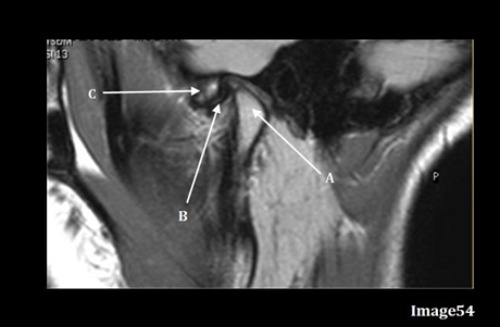

Letter A in Image 54 is pointing to:

D. Mandibular condyle

Letter C in Image 54 is pointing to:

B. Articular tubercle

Image 54 is an MRI of the ______.

C. TMJ